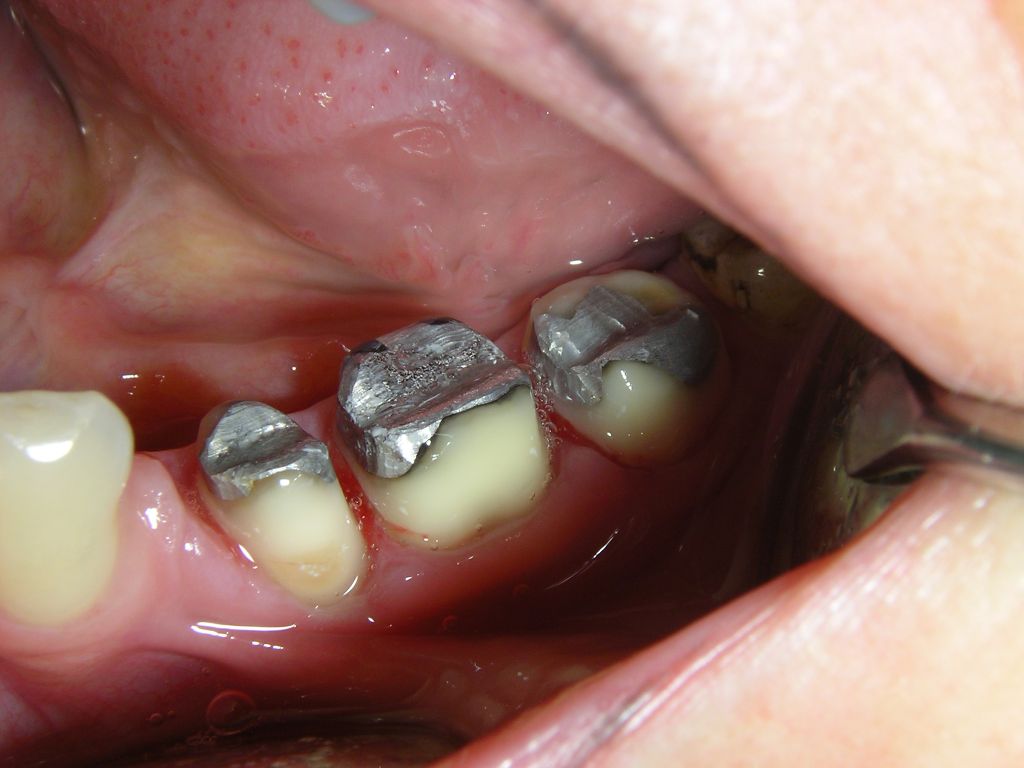

1 frische, 2 ältere Füllungen, Fissurenversiegler

Die Füllungen links wären auch in Composite gut vertretbar gewesen, die Füllungen rechts halten in Amalgam sicher länger als in Composite. Diese Amalgamfüllungen sind alle im Oberkiefer und im Alltag nicht sichtbar.